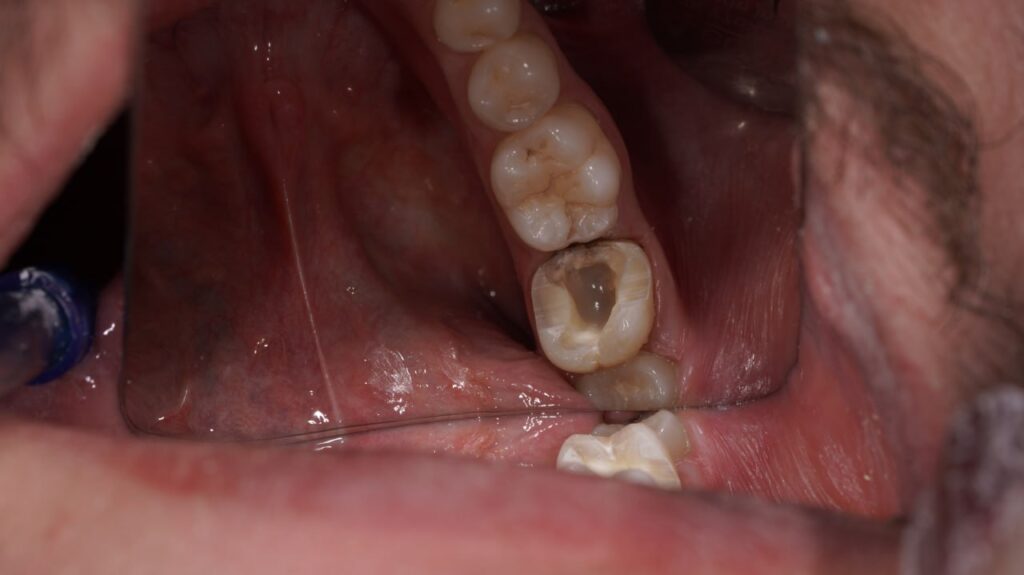

آنلی یک ترمیم سفارشی است که برای دندان‌های پشتی (آسیا) کاربرد دارد. زمانی از آنلی استفاده می‌کنیم که پوسیدگی یا آسیب، بخشی از تاج دندان را درگیر کرده باشد، اما سطوح جونده و یک یا چند تیغه جانبی دندان هنوز سالم باشند.

روکش نیز یک ترمیم سفارشی برای دندان‌های پشتی است، اما وسعت بیشتری نسبت به آنلی دارد. زمانی از روکش استفاده می‌کنیم که آسیب، یک یا چند تیغه (دیواره) جانبی دندان یا سطح جونده وسیع‌تری را درگیر کرده باشد، اما هنوز نیاز به روکش کامل نباشد.

به زبان ساده: آنلی “درون” دندان می‌رود، در حالی که روکش “روی” بخشی از دندان را می‌پوشاند. روکش نسبت به آنلی، پوشش و حمایت بیشتری از ساختار دندان به عمل می‌آورد.

این بزرگترین مزیت آنلی و روکش محسوب می‌شود. برای قرار دادن یک روکش کامل، دندانپزشک باید از تمامی سطوح دندان به مقدار قابل توجهی (حدود ۲ میلی‌متر) بتراشد. اما برای آنلی و روکش، تنها بخش‌های آسیب‌دیده و پوسیده تراشیده می‌شوند و بافت سالم دندان تا حد امکان حفظ می‌شود. این امر باعث افزایش طول عمر دندان طبیعی می‌شود.

شکنندگی نسبی مواد سرامیکی